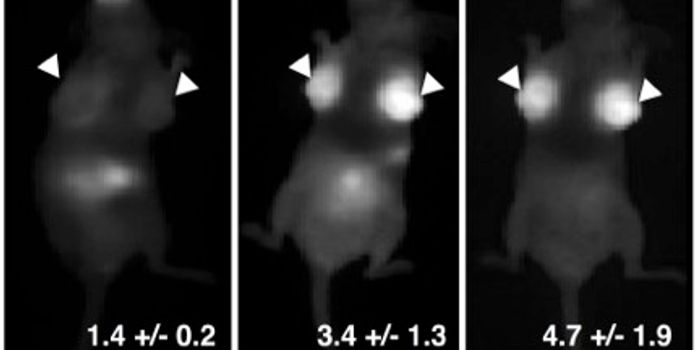

MAY 14, 2021MicrobiologyResearchers have created an imaging agent that will allow scientists and clinicians to visualize a bacterial infection c ...